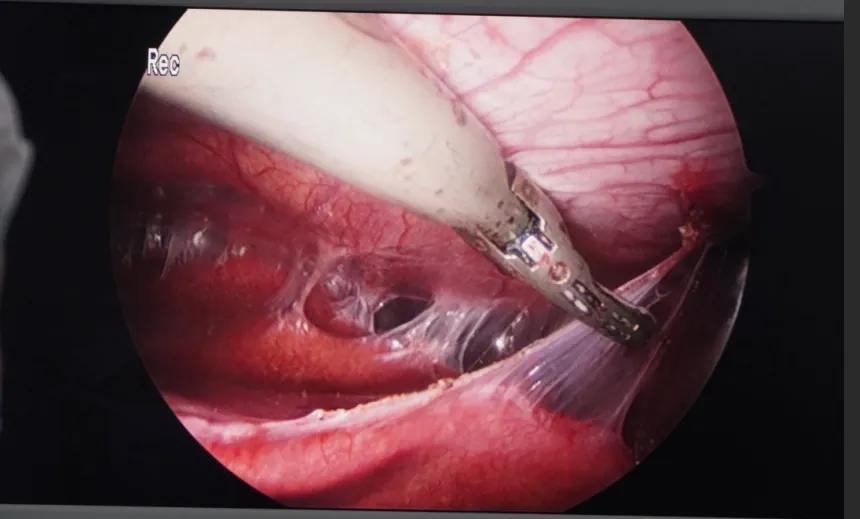

手术如期进行。当腹腔镜探入患者腹腔时,眼前的景象印证了术前的预判:腹腔内大片紧密粘连,胆囊区域完全被包裹成一片“无人区”,正常的解剖标志根本无从寻觅。特别是由于胆囊陷入肝脏,传统的“先显露胆囊三角”的方法已行不通。

面对如此棘手的状况,主刀医生果断调整策略,采取 “顺藤摸瓜、逆向剥离” 的安全术式。手术团队以胆囊底部作为突破口,从胆囊陷入肝脏的“顶部”开始,利用精细的超声刀,像考古学家清理文物一样,一点点地分离粘连,沿着胆囊的走行,小心翼翼地向着胆囊三角区域“顺藤摸瓜”进行游离。

在分离过程中,由于胆囊嵌顿在器官之间,胆管、肝总管的位置难以确认,每一步都如履薄冰。医生凭借丰富的解剖知识和稳定的手感,在粘连的“荆棘”丛中精准地找到了胆囊管与胆囊动脉。在完全确认胆总管走行无误后,医生予以妥善夹闭并离断。整个操作过程出血少,成功保留了肝脏及周围脏器的完整性,避免了中转开腹。